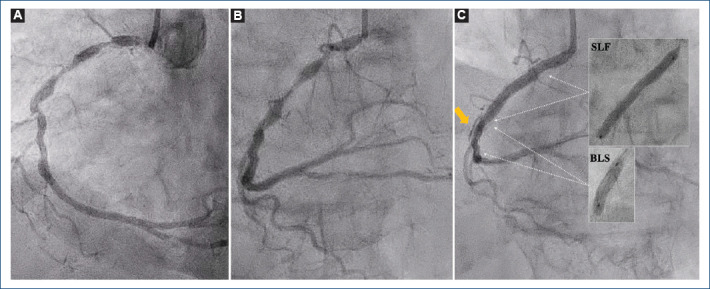

[Dislodged coronary stent: unexpectedly lost and found].

{"title":"[Dislodged coronary stent: unexpectedly lost and found].","authors":"Kristian Rivera, Gemma Mateus-Porta, Diego Fernández-Rodríguez, Luis R Puglla-Sánchez","doi":"10.24875/ACM.24000071","DOIUrl":null,"url":null,"abstract":"","PeriodicalId":93885,"journal":{"name":"Archivos de cardiologia de Mexico","volume":" ","pages":""},"PeriodicalIF":0.0000,"publicationDate":"2025-01-20","publicationTypes":"Journal Article","fieldsOfStudy":null,"isOpenAccess":false,"openAccessPdf":"https://www.ncbi.nlm.nih.gov/pmc/articles/PMC12058099/pdf/","citationCount":"0","resultStr":null,"platform":"Semanticscholar","paperid":null,"PeriodicalName":"Archivos de cardiologia de Mexico","FirstCategoryId":"1085","ListUrlMain":"https://doi.org/10.24875/ACM.24000071","RegionNum":0,"RegionCategory":null,"ArticlePicture":[],"TitleCN":null,"AbstractTextCN":null,"PMCID":null,"EPubDate":"","PubModel":"","JCR":"","JCRName":"","Score":null,"Total":0}